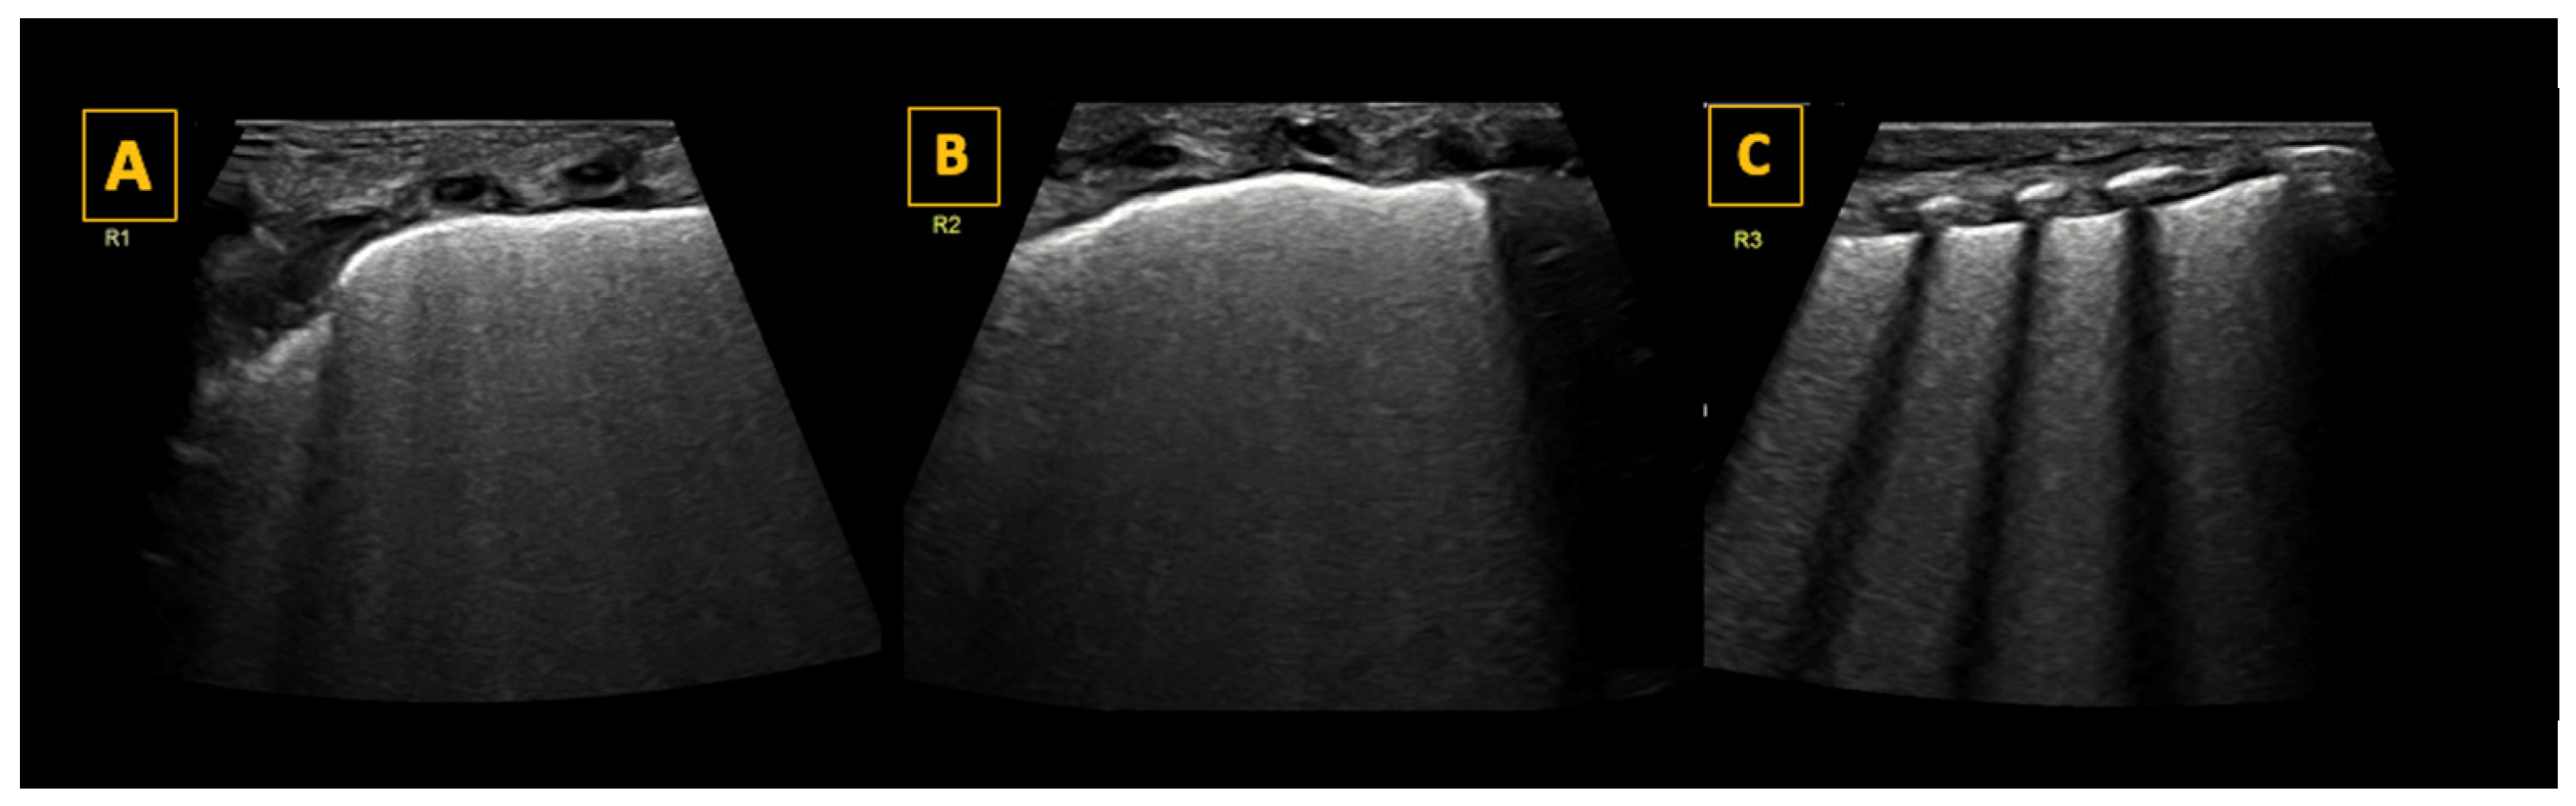

. R1 is the right upper anterior region, R2 is the right lower anterior region, R3 is right lateral, L1 is the left upper anterior region, L2 is the left lower anterior region, and L3 is left lateral, whilst RP and LP are the right and left posterior areas, respectively. The areas used for LUS are represented by red crosses in addition to the blue circles

and comprise R1, R2, R3 and L1, L2, and L3.